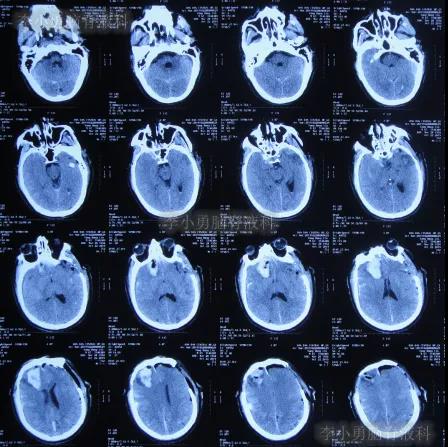

开颅术后第4天即2019年10月24日,查头颅CT示积血仍未明显减少(图-4)。

图-4:2019年10月24日头颅CT

继续治疗1周时间内,曾3次复查头颅CT(图-5、图-6、图-7)均示脑膨出逐渐加重的趋势,仍有积血;期间给予腰大池引流。

图-5:2019年10月26日头颅CT

图-6:2019年10月29日头颅CT

图-7:2019年10月31日头颅CT

图-8:2019年11月3日头颅CT

开颅术后18天即2019年11月7日,脑膨出进一步好转(图-9)。

图-9:2019年11月7日头颅CT